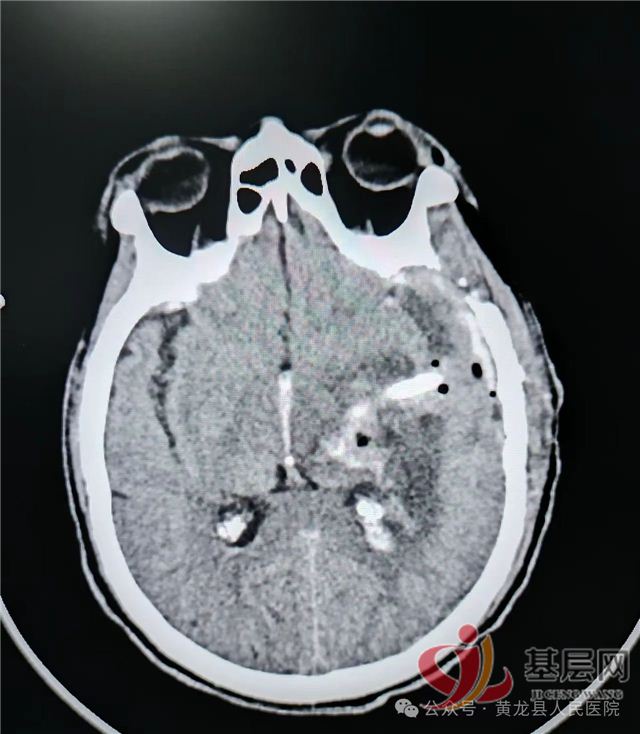

术前CT:左侧内囊--丘脑区脑出血破入脑室,出血量巨大,同侧大脑半球受压明显,脑室挤压,中线偏移

术后第1天复查:颅内血肿基本清除,脑受压减轻